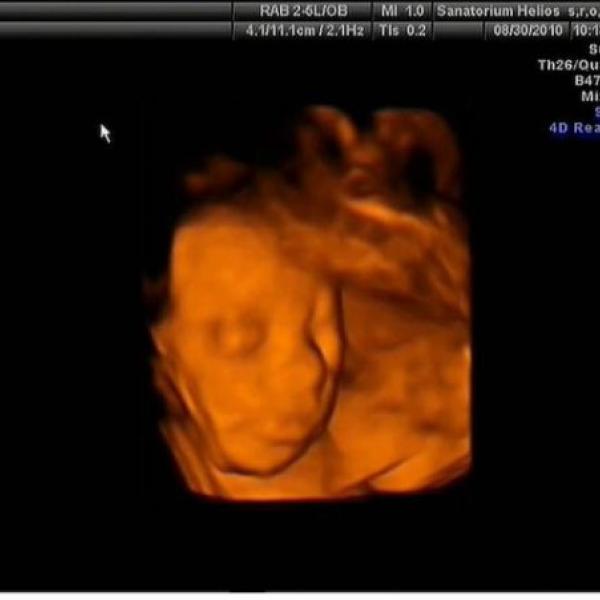

Ahoj spolutěhulinky :) tak jsem konečně taky vyfotila domeček našeho Tobíka :h: je to focené před týdnem v 30tt a už teď mi přijde, že mám pupík zase větší :00: Večer už mi vad